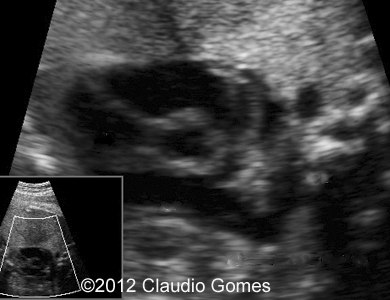

Image 1: At 21 weeks, persistent right umbilical vein ( arrow) next to gallbladder (*)

f1